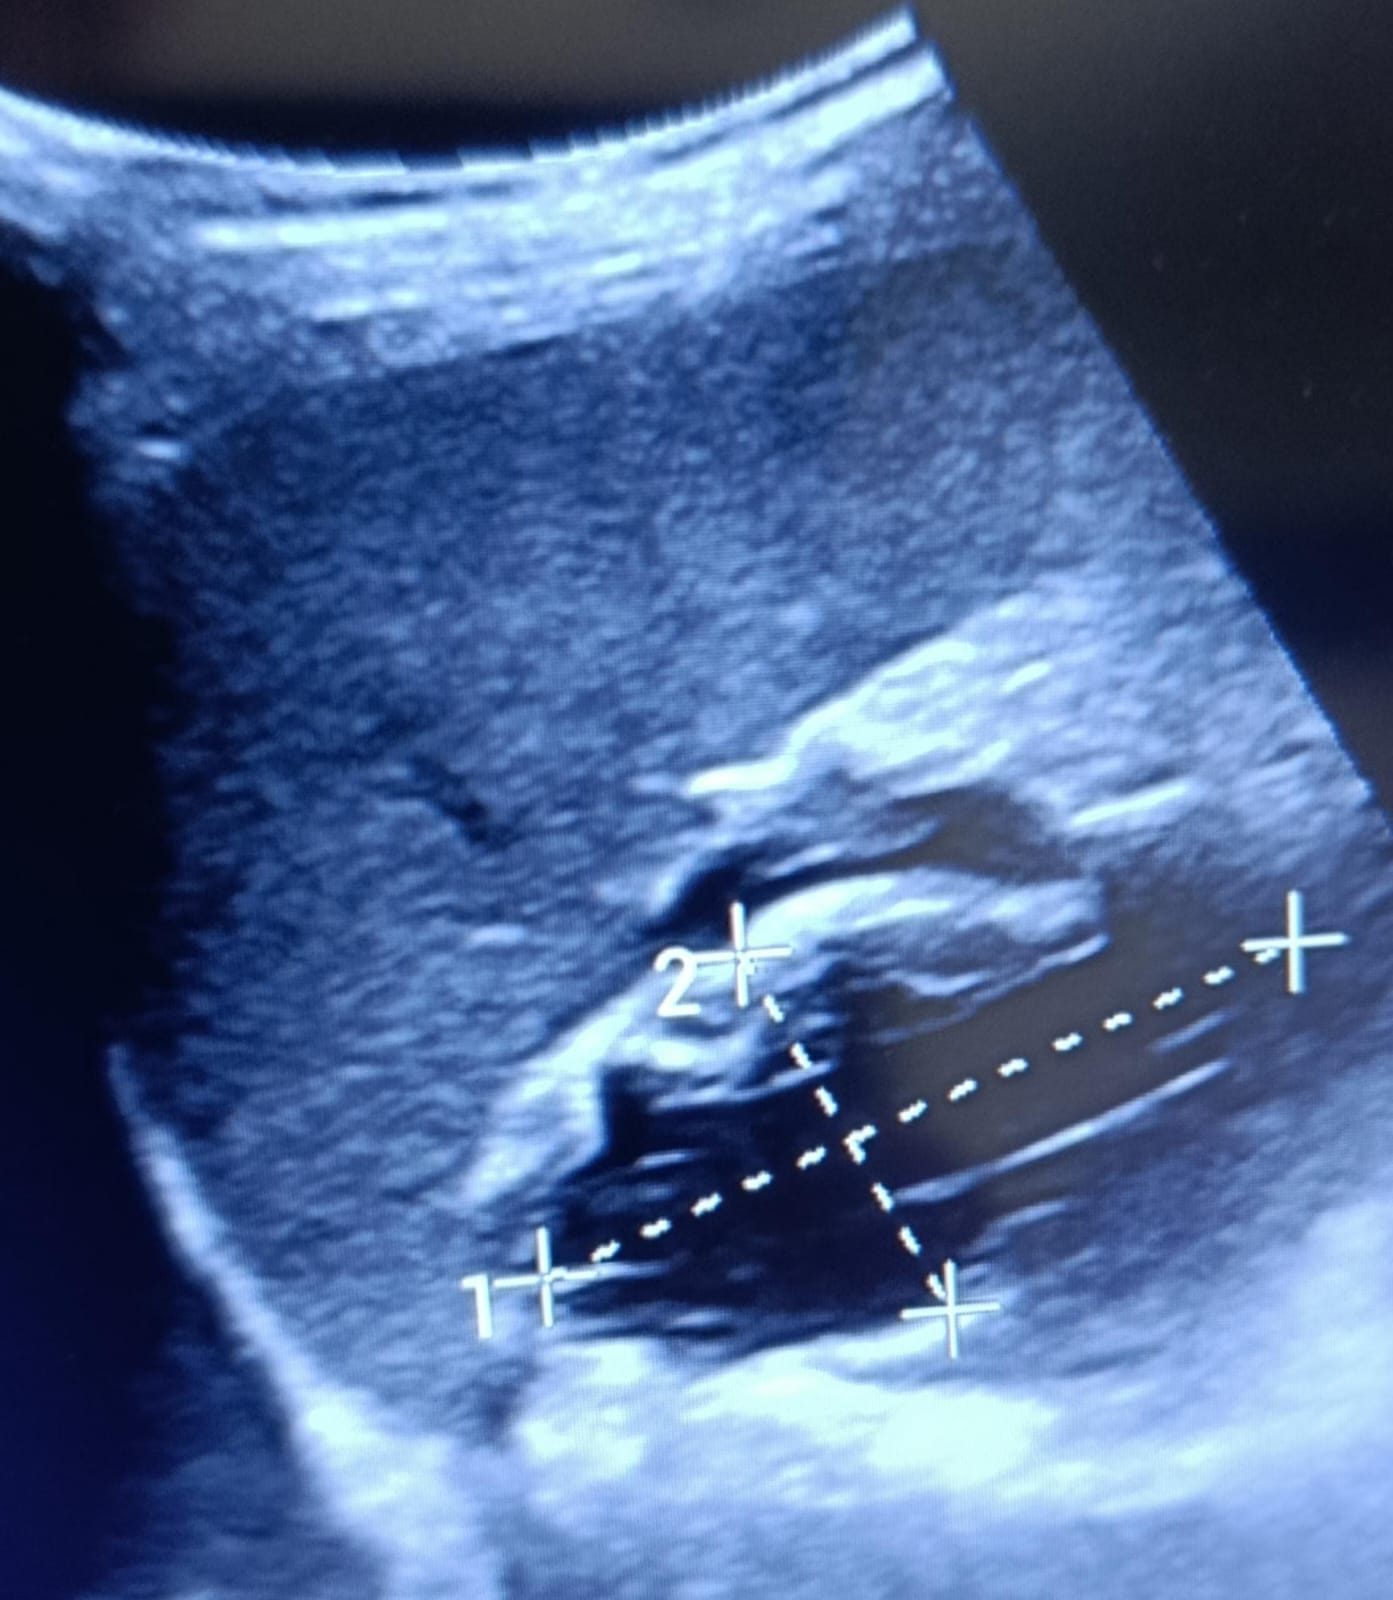

Ecografía abdominal a pie de cama: Imagen hipoecoica subcapsular en polo lateral del bazo, homogénea, compatible con hematoma esplénico subcapsular. No líquido libre intrabdominal.

Juicio clínico: Traumatismo abdominal con hematoma esplénico subcapsular.